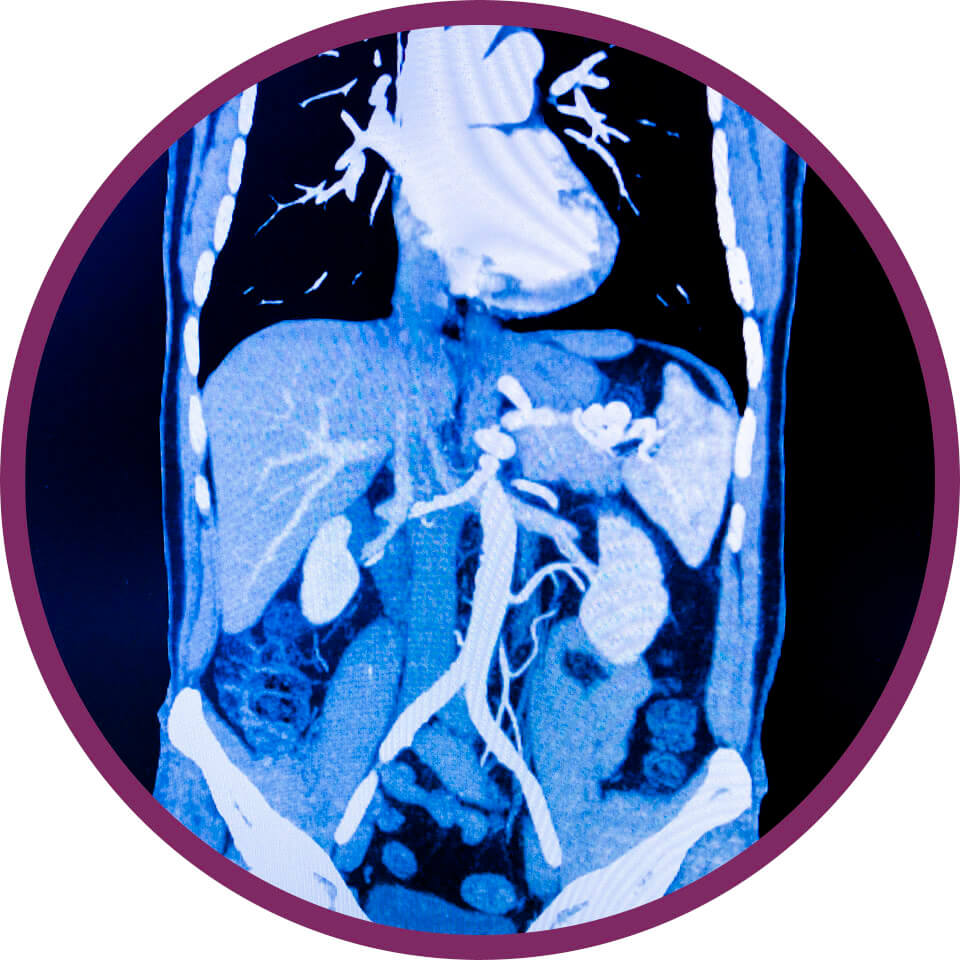

CT angiográfia,

érszűkület elzáródás

Mi a vizsgálat célja?

A kontrasztos CT angiográfia kiválóan alkalmas artériákat vagy aortát érintő érszűkületek, érelzáródások illetve körülírt érfaltágulatok (aneurysmák) kimutatására. Akár végtagi, mellkasi, hasi, nyaki vagy agyi erek esetében is elvégezhető a CT angiográfia, melyet 3D rekonstrukcióvak is ki lehet egészíteni. A CT angográfia során a vénásan bólusban magas koncentrációban, nagy sebességgel beadott speciális kontrasztanyag kirajzolja az aorta mellkasi, hasi-és kismedencei, illetve végtagi ágait és lefutását, időben követve az artériában áramló kontrasztanyag útját, s ezáltal nagy pontossággal kirajzolja az érpályát és kimutatja annak struktúrális eltéréseit. A CT angiográfia segíthet a daganatos betegségek műtéti tervezésében is.

Van mellékhatása?

A CT vizsgálatnak ritkán van mellékhatása, fájdalommentes. Kontrasztanyag adását követően érezhet melegség érzetet, fémes száj ízt, gyógyszer ízt a szájban, illetve vizelési ingert. A lehetséges mellékhatásokról, pácienseink szóban és írásban kapnak tájékoztatást.

Milyen előkészület szükséges?

A CT angiográfia vizsgálat előtt fontos a kezelőorvossal, családorvossal, belgyógyász szakorvossal vagy angiológus érsebész szakorvossal történő konzultáció, hisz a CT vizsgálat során, sugárterhelés illetve kontrasztanyag adása történik, így a vizsgálatot csak orvosi javaslat alapján végezzük. A kontrasztanyag adása a CT angiográfia elengedhetetlen alapja, ezért a vizsgálat előtt 6 órával már nem szabad enni. A kontrasztanyag adása előtt meg kell vizsgálni a vese működését jelző labor paramétereket, mivel súlyosan károsodott (beszűkült) vesefunkció esetén a kontrasztanyag adása lehetőség szerint elkerülendő. Ismert kontrasztanyag allergia esetén a kontrasztanyag adása tilos (kontraindikált). A kontrasztos vizsgálatok előtt a metformin tartalmú cukorbetegségben adott gyógyszerek szedését be kell szűntetni.

Hogyan végezzük a vizsgálatot?

A CT angiográfiás vizsgálat célozható az agyra, a nyakra, a mellkasra, a hasra, a kismedencére, a végtagokrta vagy az egész testre is az érpálya lefutásának megfelelően. A CT angiográfia során a beteg véna kanüljébe nagy nyomással és sebességgel beadott magas koncentrációjú kontrasztanyag útját követjük a szíven és tüdőn keresztül a nagyvérkör irányában, azáltal láthatóvá téve az aortát, annak teljes lefutását, valamint az aorta elsődleges, másodlagos és tercier ágrendszerét. Az artériás érhálózat lefutását és struktúrális eltéréseit 3 dimenzióban is ábrázolhatjuk és követhetjük. A CT angiográfiás eljárás a kontrasztos CT vizsgálatnál is érzékenyebben és pontosabban mutatja az erek struktúrális eltáltozásait, ezen belül is elsősorban az érelmeszesedés okozta érszűkületeket, az érleszorításokat, az érelzáródásokat és az orsószerű értágulatokat (aneuryzma), valamint az erek belhártyájának érfalról történő leválását (disszekció).